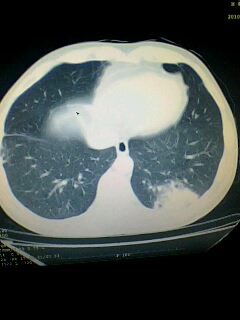

标题: CT28315:咳嗽咳痰咯血半月并胸痛 [打印本页]

标题: CT28315:咳嗽咳痰咯血半月并胸痛

1、纵膈窗效果不好,初步考虑左肺下叶感染性病灶,建议正规抗炎治疗后复查   2、右肺下叶陈旧性病灶伴局部胸膜增厚。

左下肺肿块影,深分叶,考虑肺癌。

左下肺球形病灶,考虑:1:球形肺炎;2:周围型肺癌不除外,建议治疗后复查

不排除左肺下叶周围型肺癌可能!建议穿刺活检!

考虑左肺下叶周围型肺癌并阻塞性肺炎。